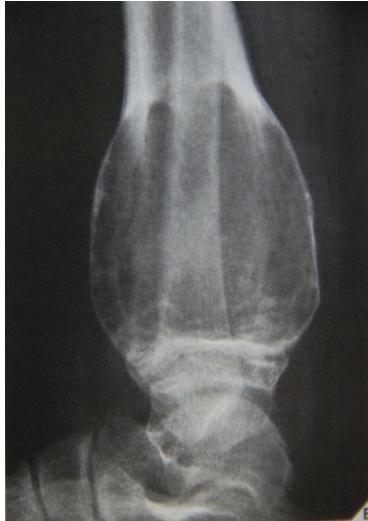

Aneurysmal Bone Cyst

site: Distal tibial

size: Involving most of distal part

matrix: Cortical expansion, radiolucent matrix, well defined, narrow zone of transition

soft tissue involvement: no peristeal reaction